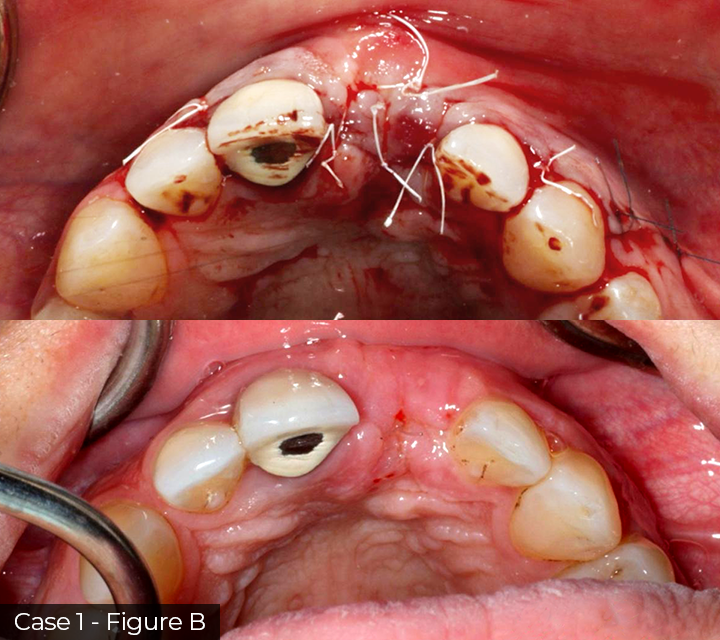

Director’s Clinical Cases

Director’s Clinical Cases